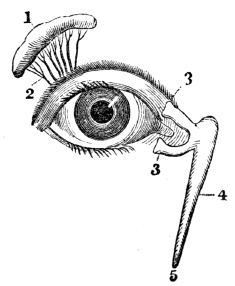

| 44. | Anatomy of the Organs of Vision, | 394 |

| 45. | Physiology of the Organs of Vision, | 404 |

| 45. | Hygiene of the Organs of Vision, | 410 |